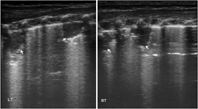

本组MAS患儿的肺脏超声主要表现(表1):(1)肺实变伴支气管充气征:见于所有患儿,重度患儿通常为范围较大、且边界不规则(锯齿状边缘)的实变区(图2,图3,图4);而轻度患儿则以小范围的局限性实变为主要表现(图5);但双侧肺脏实变范围的大小可以不同,而且同一侧肺脏野可以存在大小不同的实变区(图4,图5,图6)。(2)胸膜线异常与A-线消失,见于所有患儿,胸膜线异常表现为病变区胸膜线消失或增粗模糊(图2,图3,图4,图5,图6)。(3)肺不张,是严重肺实变的表现,见于重度患儿,本组12例(17.9%)(图7),严重大面积肺不张时可在实时超声下见到肺搏动和动态支气管充气征。(4)胸腔积液,见于9例(13.4%)患儿(图7)。(5)B-线或AIS,在实变区以外肺野则以AIS或B-线为主要表现。

MAS具有典型的肺脏超声影像学改变。主要特征如下:(1)肺实变伴支气管充气征,见于所有患儿。通常重度患儿实变范围较大、边界不规则呈锯齿状,支气管充气征也较为明显;而轻度MAS则为较小范围的局灶型实变。(2)双侧肺脏或同一侧肺脏不同肺野病变性质与程度的不一致性,双侧肺脏可有范围不同的实变区,同一侧肺脏不同肺野也可以存在大小不同的实变区。(3)肺不张,见于少数重症患儿,更为严重者在实时超声下可见肺搏动或动态支气管充气征。(4)胸膜线异常,表现为病变区胸膜线消失或增粗、模糊。(5)A-线消失,所有患儿在实变区和非实变区均不见A-线。(6)B-线或AIS,非实变区肺组织在超声下常表现为B-线或AIS。(7)胸腔积液,轻度或重度MAS患儿均可有胸腔积液,本组见于13.4%的患儿。但上述超声表现也可见于RDS、肺不张和TTPN等肺病,虽均非MAS的特有改变,但均有各自的特点,超声很容易对它们做出诊断和鉴别诊断[4,5,6,7]。但在肺炎、尤其重度肺炎时,肺脏超声也表现为边界不规则的大面积肺实变[7,15],如无一定经验,仅靠超声表现有时难以将二者准确区别。因此,在借助超声诊断MAS与重症感染性肺炎时,往往需要结合病史。